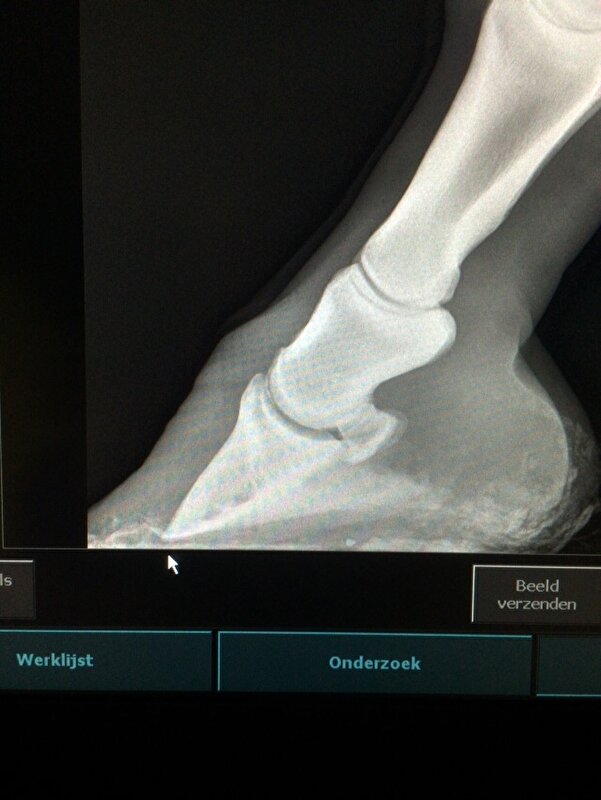

Dus volgens mij werkt het. nuvel schreef:Had gister gebeld maar er was nog niks klaar. Net heb ik de foto's gekregen van beide voorvoeten en het ziet er niet zo goed uit. Beide hoefbenen zijn gekanteld. De ene als je er voor staat is het het linker voorbeen daar komt het hoefbeen bijna door de zool. Als je er voor staat het rechter voorbeen heeft nog een cm voor hij door de zool komt.

Zal straks de rontgenfoto's en foto van het paard hier plaatsen. Ga ze nu eerst naar de kliniek sturen want wil er voor vechten. Dit paard is te sterk en te vrolijk om nu de handdoek in de ring te gooien. Ze staat op dubbele pijnstiller om nu niet te hoeven lijden.